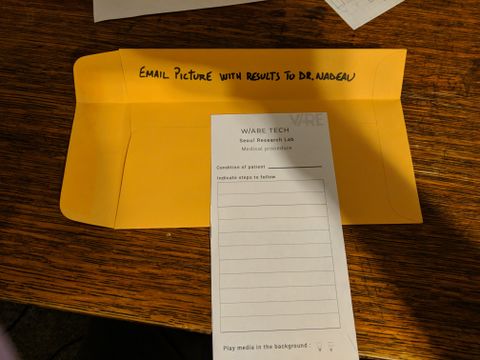

- A letter to Arnaud requesting that a picture with results be emailed to Dr. Nadeau. This included a W/ARE Tech medical procedure slip

- A plastic holographic pyramid, designed to display "3D Holograms" using a phone